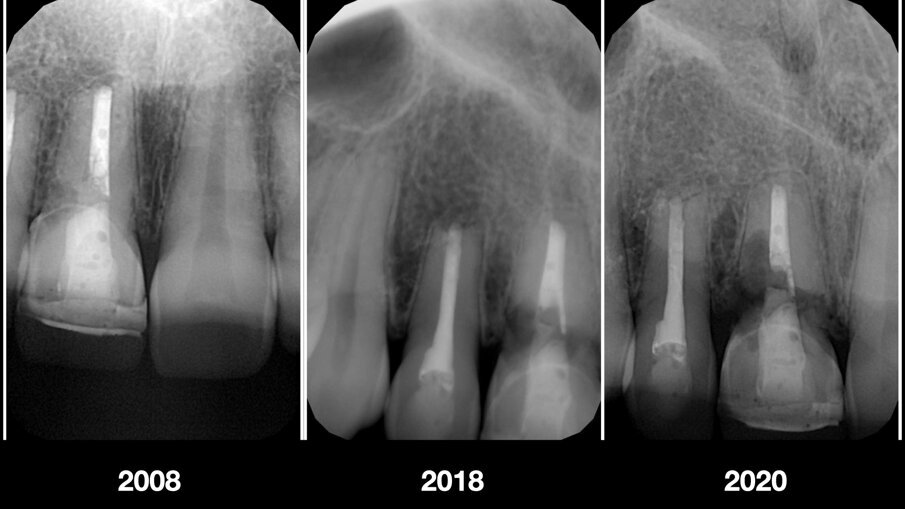

In seguito ad un riassorbimento radicolare esterno, una giovane paziente di 28 anni danneggia irreversibilmente il dente 1.1. È presente una fistola vestibolare e la sequenza radiografica mostrava un progressivo danno a carico della radice con coinvolgimento del tronco radicolare e del terzo cervicale del dente (Figg. 2-5).

Fig. 5_Radiografie intraorali iniziali.